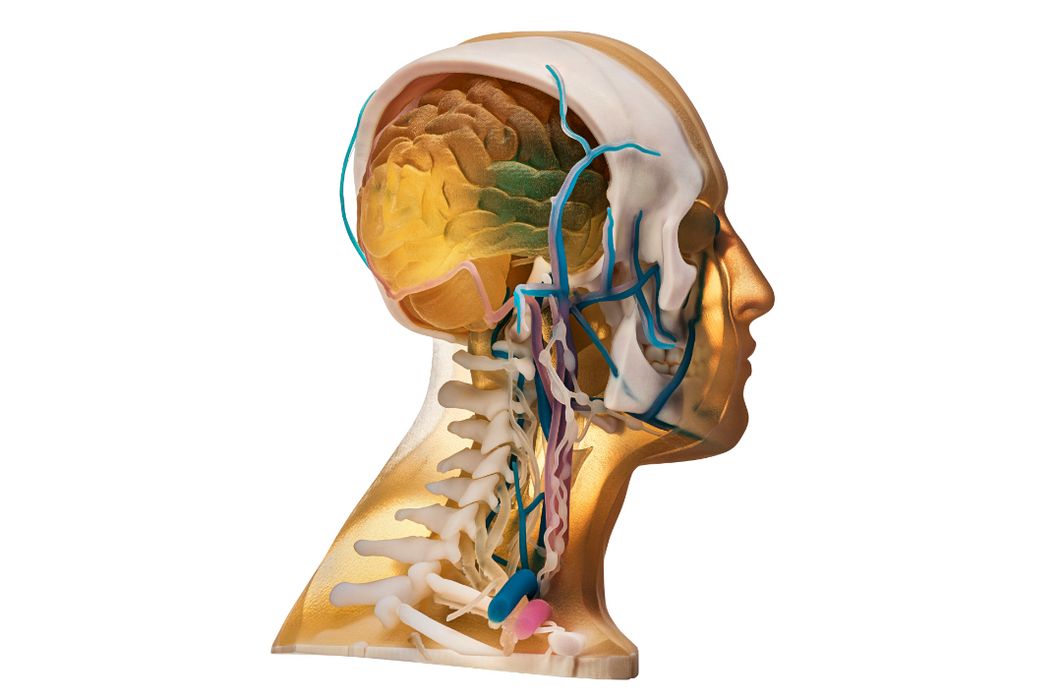

Stratasys, These 3D Prints Are Too Realistic!

Sometimes technology is going just too far.

Design of the Week: Ultra Realistic 3D Printed Head

This week’s selection is the incredibly realistic full color head by Stratasys.

Stratasys Direct Now Offers Anatomical 3D Printing

Stratasys Direct announced new anatomical consulting and 3D printing services.

Examining Mixed Dimension’s Anatomical 3D Prints

I got my hands on a fantastic full color, transparent 3D print from Mixed Dimensions and it’s worth discussing.